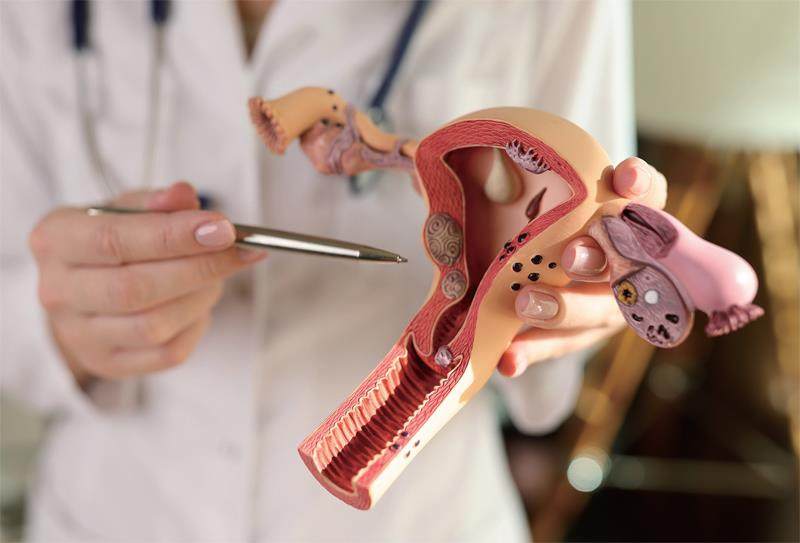

健康广角 | 别被骗了,宫颈糜烂不是病

健康广角 | 别被骗了,宫颈糜烂不是病